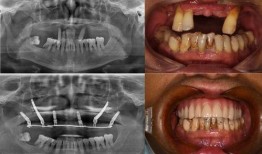

佛山种牙爆料事件最新,揭露行业乱象,患者权益如何保障?

最近佛山那边的种牙事件可是闹得沸沸扬扬的,咱们得好好来聊聊这个话题。你有没有想过,一颗牙齿的种植竟然能引发这么大的波澜?那就让我...

2025-11-27 85